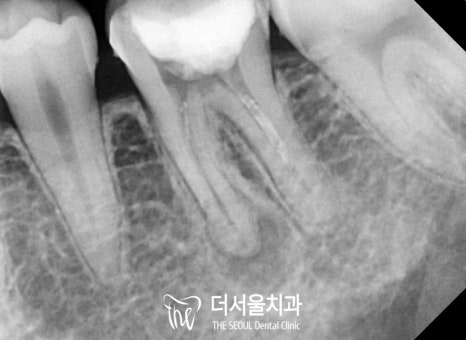

“ 신중하고 꼼꼼하게 ”

한번 진료를 받았던 곳을

또다시 리엔도로 살린다는 게..

생각보다 정말 어려운 일입니다.

채워져 있는 충전재를 제거하는 것부터

정말 신중하고 꼼꼼하게 해야 되는데요.

1) 미처 제거되지 않은 곳이 있거나

2) 충전재가 꼼꼼하게 안 채워졌을 때

3) 미세한 부근관 등을 찾지 못했을 때

이런 경우에는 병소가 재발하거나

부작용이 생길 수 있습니다.

성남 치과 에서는

한 번에, 확실한 개선을 돕기 위해

세척부터 충전 과정까지

신중하게 도와드렸습니다.

병소의 크기도 점점

줄어드는 것을 볼 수 있는데요.

다행히 성공적으로 마칠 수 있었습니다.